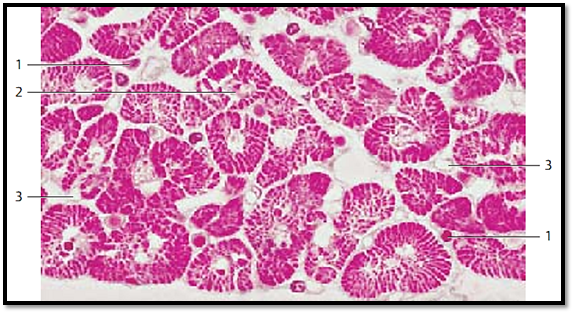

Cardiac Muscle—Myocardium—Left Ventricle

This is another cross-section through the cardiac muscle tissue, which gives a clear picture of the Cohnheim grouping . Here, myofibrils have aggregate d to lamella in a radial formation. The sarcoplasm-rich spaces are free of fibrils and appear light. The size differences among nuclei should be noted 2 . In the sparse connective tissue between heart muscle cells are f ibrocytes and capillaries. It should also be noted that the apparent variations in the diameters of the cardiac muscle f ibers (cardiomyocytes ) depend on the presence or absence of their cell nuclei in the section.

1 Nucleus of a connective tissue cell

2 Nucleus of a cardiac muscle cell

3 Capillary

Stain: alum hematoxylin; magnification: × 600